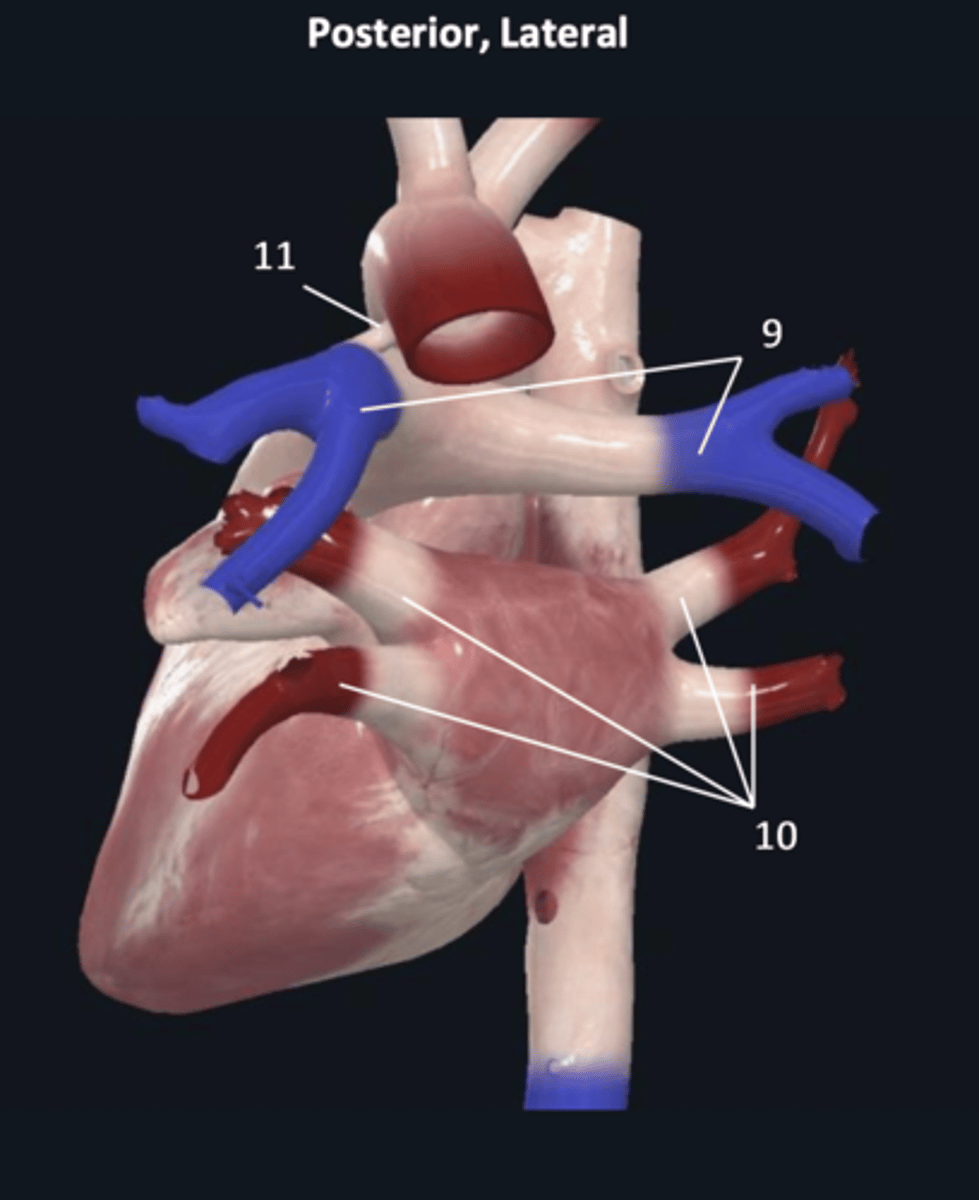

pulmonary trunk

8

pulmonary arteries

9

pulmonary veins

10

ligamentum arteriosum

11

right coronary artery

1 (red)

great cardiac vein

3

posterior left ventricular artery

6

posterior vein of left ventricle

7

coronary sinus

8

right posterolateral artery

9

middle cardiac vein

10

posterior interventricular artery

11

right marginal artery

12

small cardiac vein

13